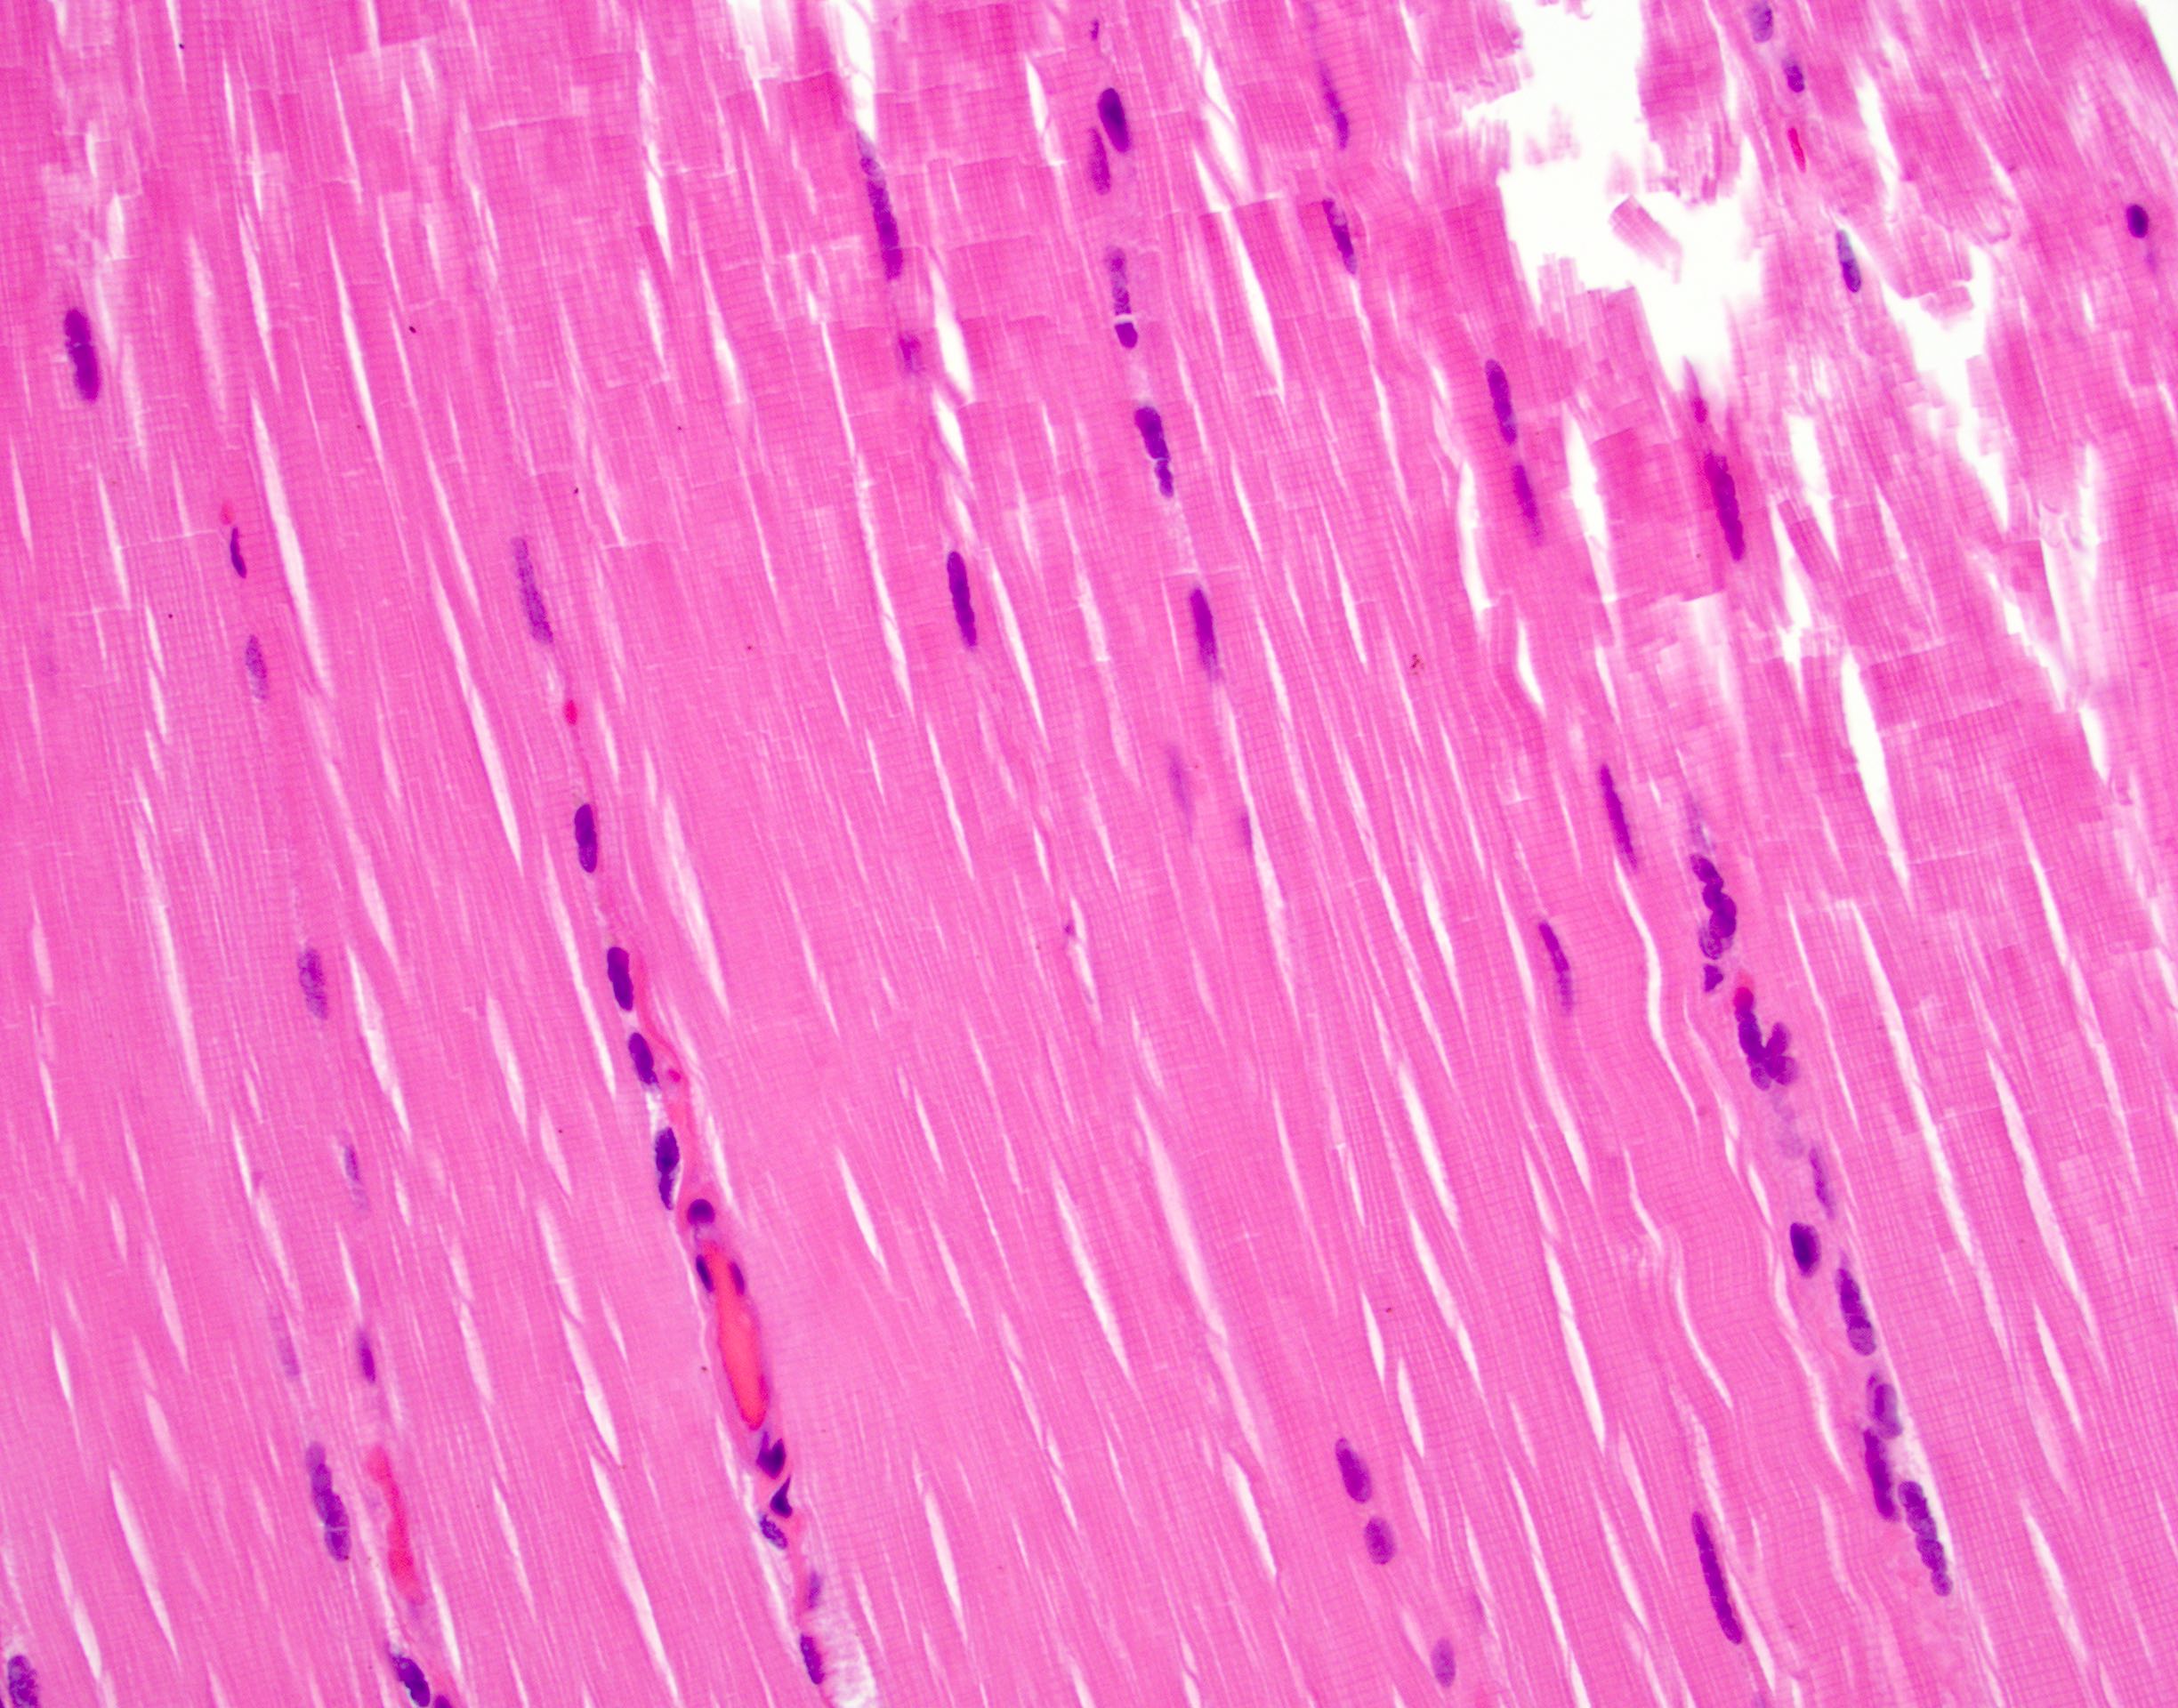

Cardiac Muscle

1Striations

2Central nuclei

3Branched fibres

+1 more points